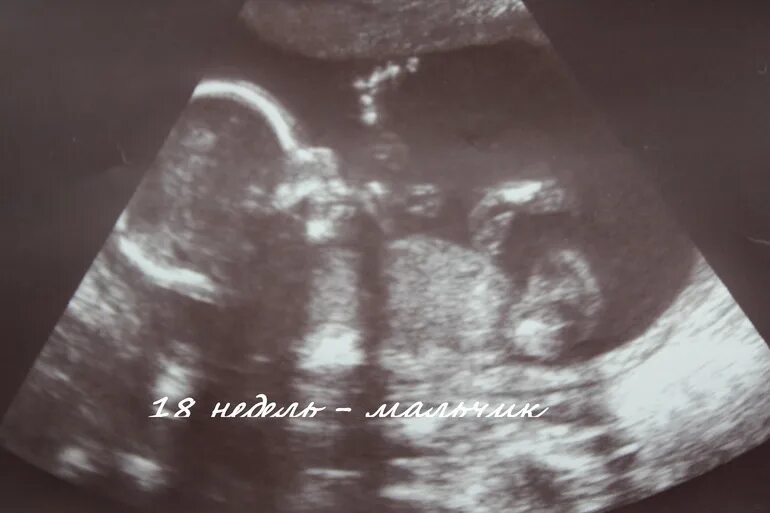

Узи 17 недель девочка